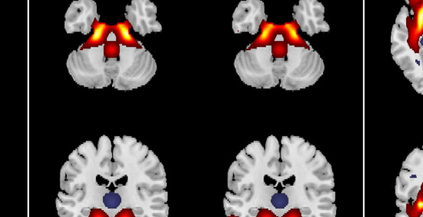

In the last two decades, unsupervised latent variable models---blind source separation (BSS) especially---have enjoyed a strong reputation for the interpretable features they produce. Seldom do these models combine the rich diversity of information available in multiple datasets. Multidatasets, on the other hand, yield joint solutions otherwise unavailable in isolation, with a potential for pivotal insights into complex systems. To take advantage of the complex multidimensional subspace structures that capture underlying modes of shared and unique variability across and within datasets, we present a direct, principled approach to multidataset combination. We design a new method called multidataset independent subspace analysis (MISA) that leverages joint information from multiple heterogeneous datasets in a flexible and synergistic fashion. Methodological innovations exploiting the Kotz distribution for subspace modeling in conjunction with a novel combinatorial optimization for evasion of local minima enable MISA to produce a robust generalization of independent component analysis (ICA), independent vector analysis (IVA), and independent subspace analysis (ISA) in a single unified model. We highlight the utility of MISA for multimodal information fusion, including sample-poor regimes and low signal-to-noise ratio scenarios, promoting novel applications in both unimodal and multimodal brain imaging data.